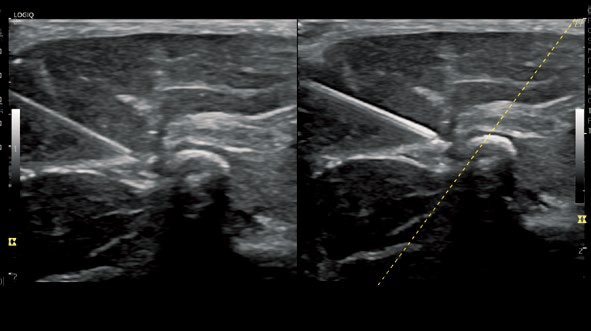

B-Steer+

穿刺針を強調し、クリアに針先を描出することで、

安全で正確な穿刺をサポートします。